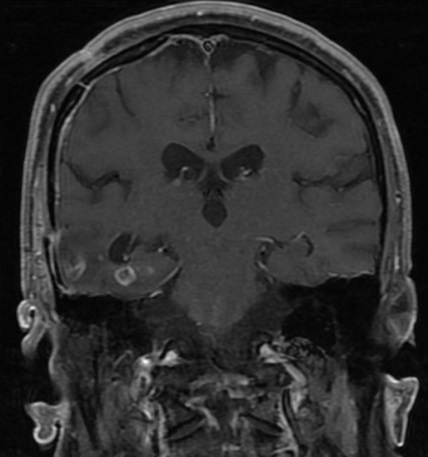

El primer año de residencia me tocó atender a un investigador italiano radicado en México, investigador emérito (física y matemáticas) con diagnóstico de glioblastoma multiforme recurrente. Se hospitalizó para resección (por tercera vez) aunque ya había recibido quimioterapia y radioterapia.

El glioblastoma había iniciado en el lóbulo temporal, pero se había extendido rápidamente, con pobre respuesta a tres modalidades terapéuticas (cirugía + radioterapia + quimioterapia). Como la mayoría de los tumores de este tipo, el pronóstico es muy pobre. Siempre que lo veía en consulta me platicaba de su investigación en física y tenía sus propias teorías (llenas de fórmulas matemáticas que nunca logré entender) sobre el comportamiento biológico de su tumor. Cuando se hospitalizó, sus dos hijas tomaban turnos para cuidarlo, nunca lo dejaban solo. En su cuarto siempre tenían varios libros de arte y me llamó la atención uno de Vincent van Gogh.